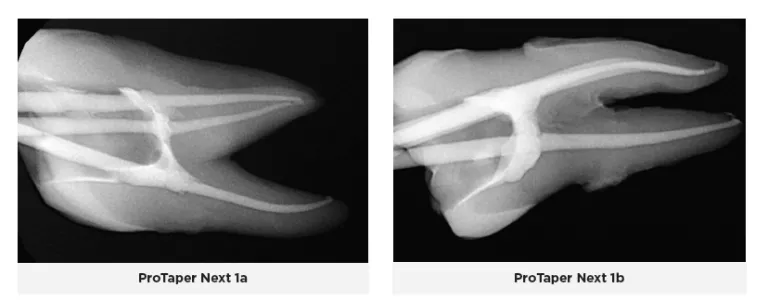

Similar to the ProTaper Gold design, the ProTaper Next files have a progressively percent tapered design on a single file(16). However, the ProTaper Next files use M-wire technology which improves resistance to cyclic fatigue, decreases the risk for file separation, and increases flexibility(16). Additionally, these files have an offset mass of rotation so that the file contacts the canal wall at 2 points(16). This offset mass of rotation decreases taper lock, allows more cross-sectional space for more efficient cutting and debris removal, and allows a smaller more flexible file to cut a same sized preparation as a larger and stiffer file with a centered mass and axis of rotation(16).

ProTaper Next files with M-Wire technology have been shown to cut dentin very well, but with subsequent use, there might be significant coronal, mid-root and apical canal transportation as well as an increase in the overall canal volume(17). This results in a loss of the original anatomy of the canal.

Observations noted when using ProTaper Next during this trial were that the file system cuts more efficiently and is more efficient in the number of steps than the ProTaper Gold system. The X1 and X2 files were more flexible than the X3, however, without controlled memory, they would still straighten out and transport the canal. The X3 file grabs and binds the tooth structure even more and takes away from the natural contour and anatomy. The ProGlider file followed the natural anatomy of the canal much more so than the ProTaper Next files. Because they lack controlled memory, the files are more likely to ledge and transport the canal, and they also tend to bind along multiple points within the canal which leads to an increased risk of separation. They do a lot of chipping and cutting of dentin from the canal walls, so you constantly have to irrigate out debris and recapitulate; because if not, you can easily lose patency.

Obturation with the fitted gutta-percha went to working length and fit the canals well in most cases; however, the gutta-percha extended out the apex in one canal because of a larger anatomical foramen, and the gutta-percha stopped short in six other canals. Three of those canals had ledging caused by the X1 and X2 files and patency could not be regained, so the gutta-percha could not reach the full working length. And, in one instance, the gutta-percha stopped short, but upon re-instrumentation of the canal three more times, the gutta-percha was able to be seated to the full working length.

Two dimensional radiographs were taken of the teeth after endodontic therapy was completed and reviewed. In some of the ProTaper Gold and Next cases, working length was not reached radiographically, even though it was thought to be achieved clinically. As an electronic apex locator cannot be used to assess working length on extracted teeth, working length was established with visual observation. Clinically, an electronic apex locator would have been used, and adjustments would have been made throughout the entire process to ensure the working length was reached. The teeth were selected at random, and some of the orifices and canals were calcified or stenotic. In a live clinical scenario, ultrasonics would have been used to negotiate these constrictions more easily; however that being said, the ZenFlex and Traverse file systems allowed these canals to be negotiated and treated without issue. Additionally, the teeth treated with the ZenFlex files appeared to have the best preservation of the natural shape of the canal and conserved the most tooth structure. This was not the case with the ProTaper Gold and Next file systems. Less efficient cutting with more aggressive removal of tooth structure was noted, resulting in a loss in the original anatomy of the canals. ZenFlex is an ideal file that balances strength and flexibility to allow clinicians to reach the working length while being minimally invasive, even in cases with complex canal anatomies.